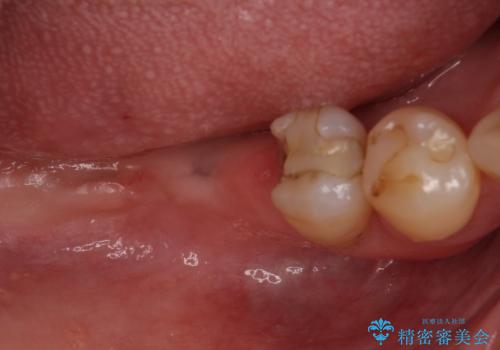

診察したところ、前歯は反対咬合であり、その影響で抜歯が必要な奥歯があることが分かりました。

抜歯が必要な奥歯は、インプラント並びにブリッジにより補綴を行い、上下前歯は反対咬合を改善させるように補綴治療を行うこととしました。